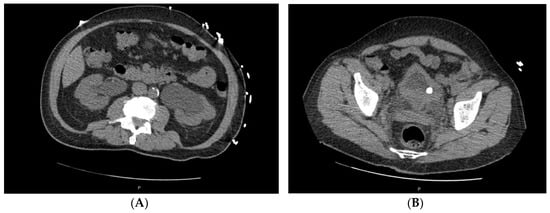

2. Case Series